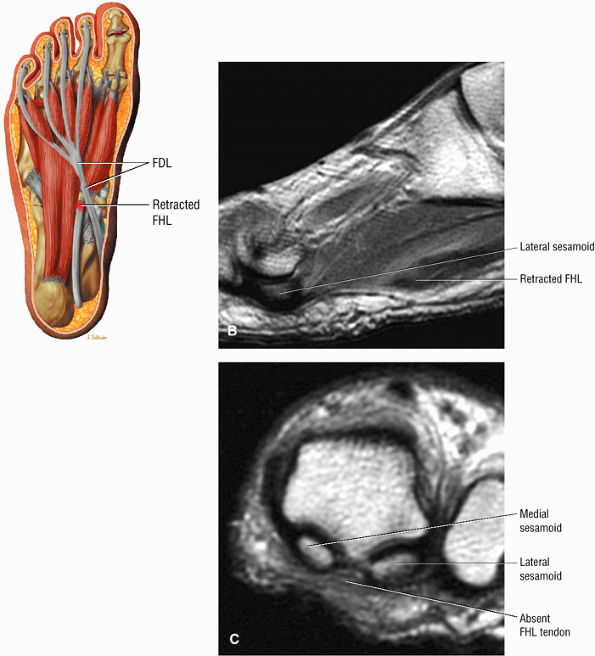

FIGURE 5.9 ● FLEXOR HALLUCIS LONGUS The flexor hallucis longus (FHL) flexes the great toe and plantarflexes the foot. The FHL is susceptible to injury during extremes of ankle plantarflexion and metatarsophalangeal dorsiflexion. The proximal sheath, 10 to 12 cm in length, has no mesotenon and may communicate with both the ankle joint and the sheaths of the flexor digitorum longus and tibialis posterior.